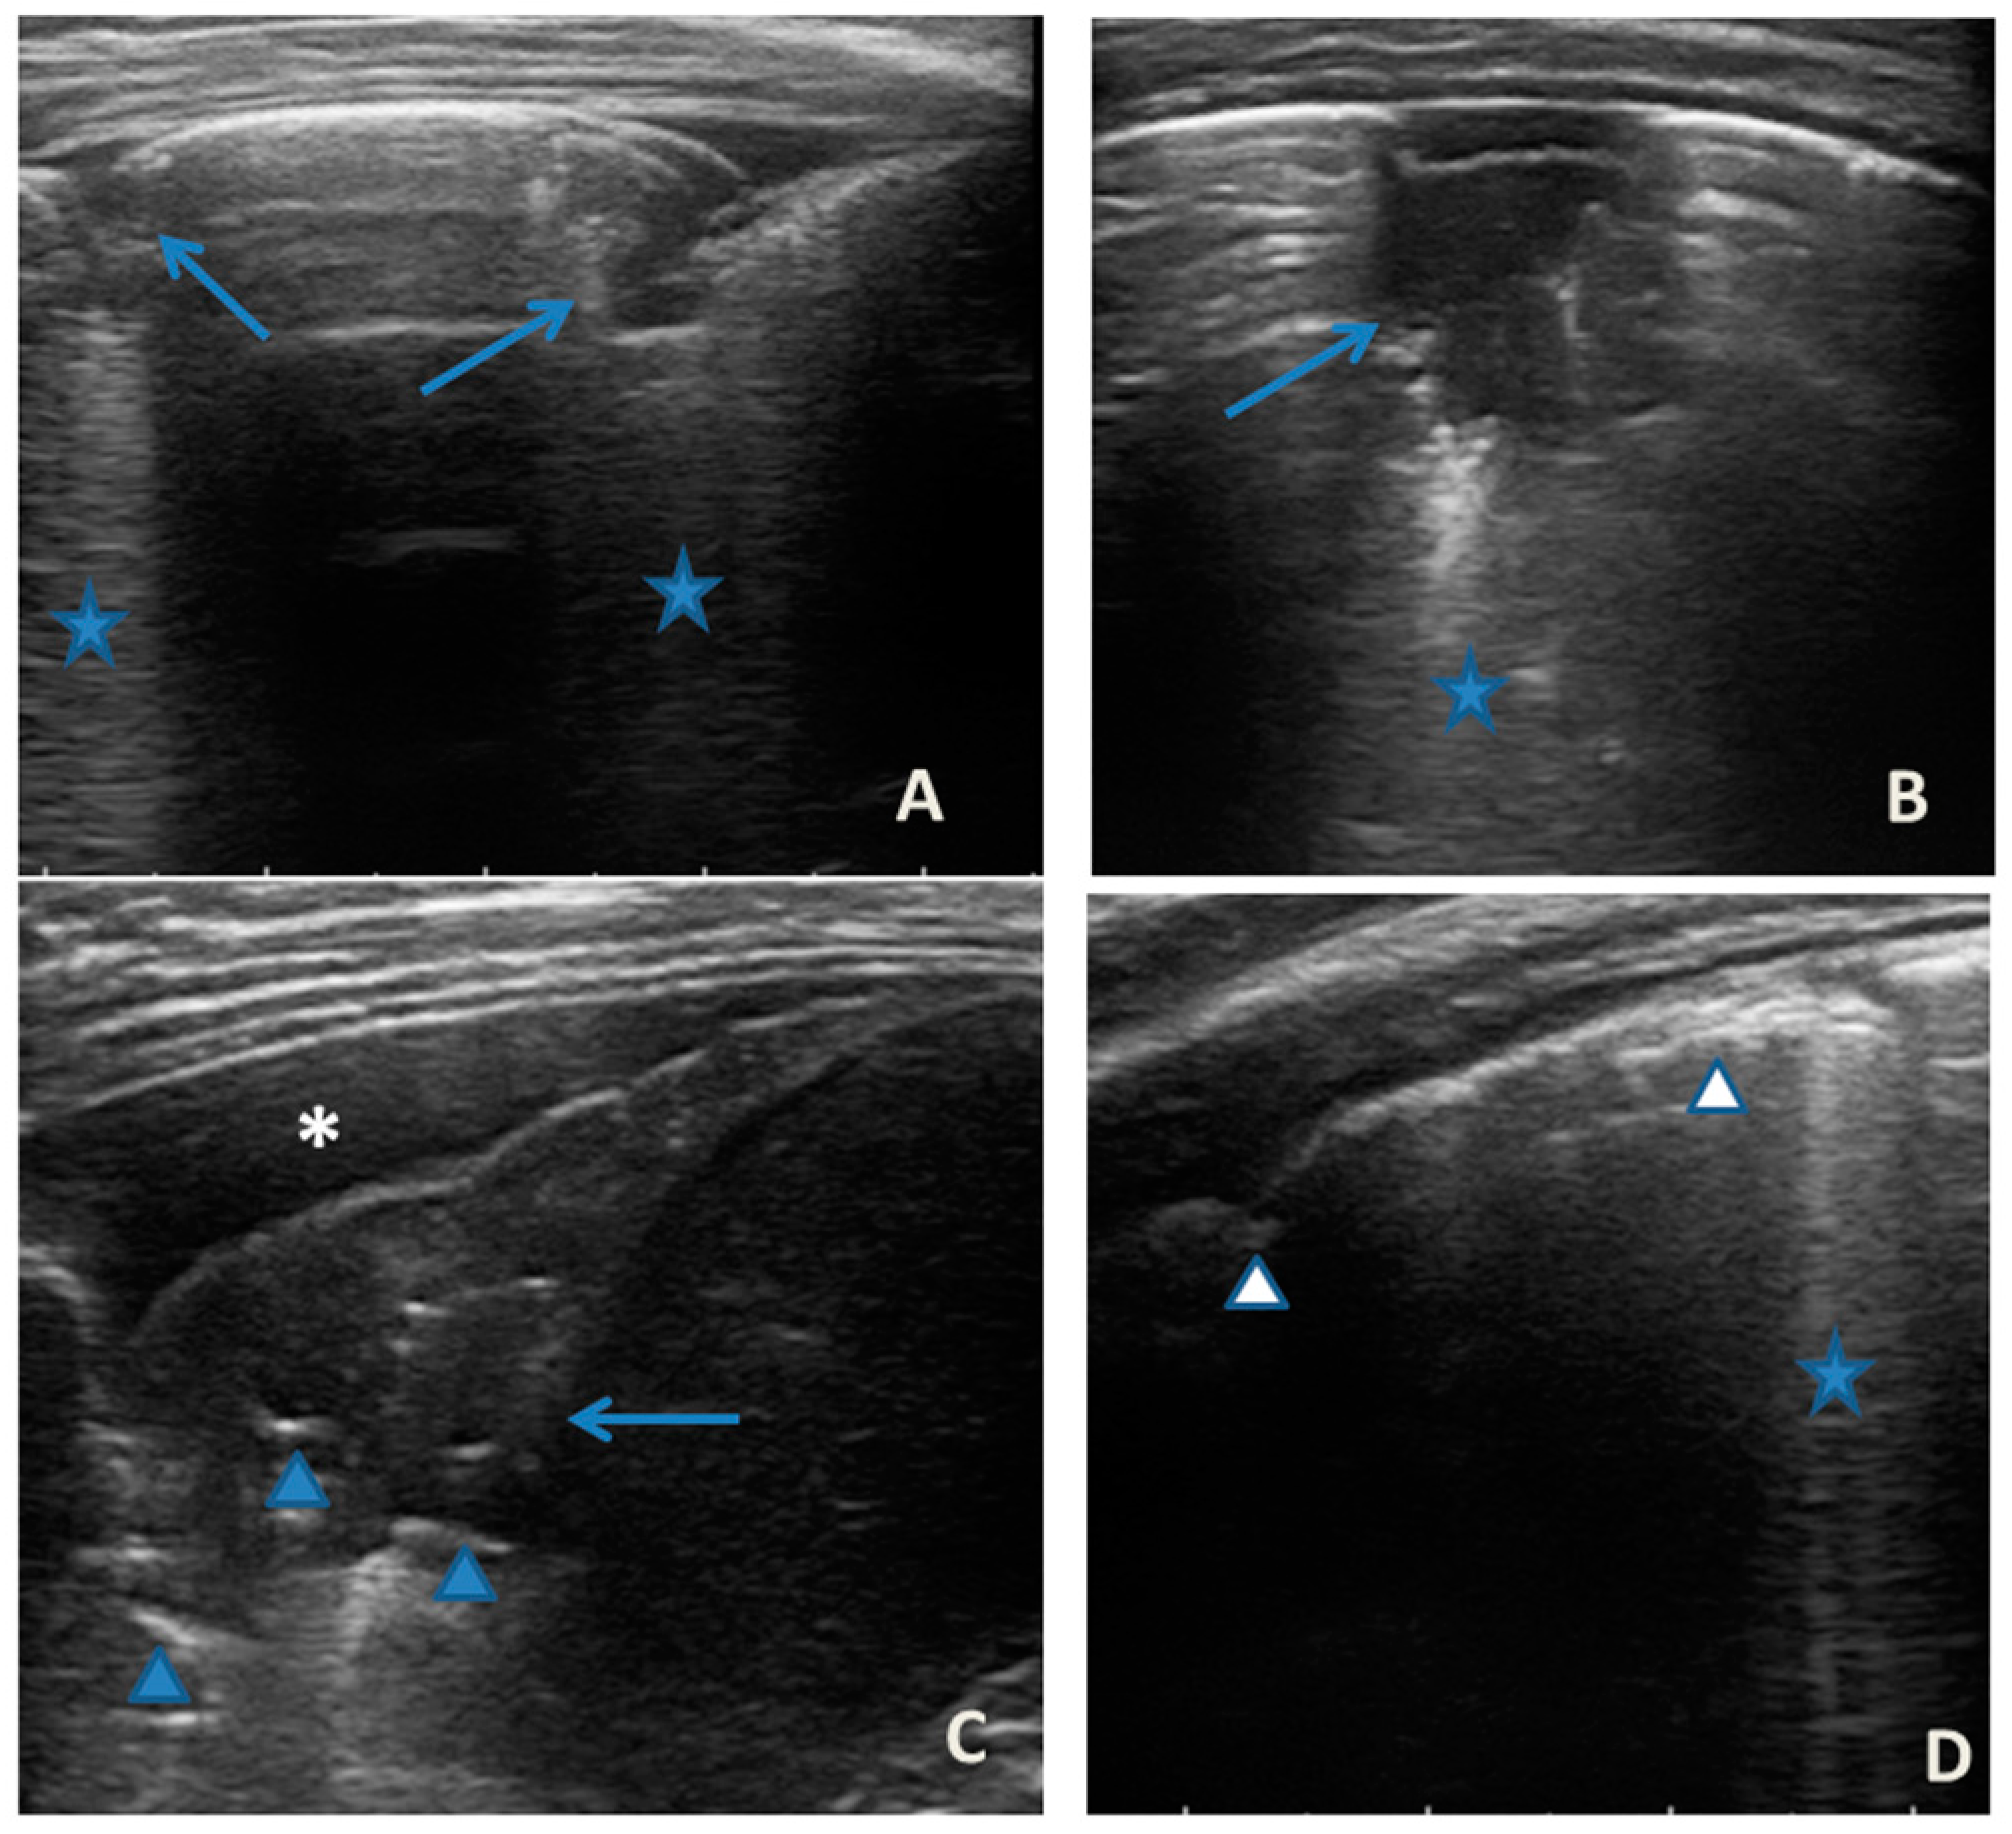

In any case, therapy for acute asthma attack and antibiotic therapy was set up, and he was admitted to the pediatric ward. Here, at the same time as the clinical evaluation, we performed LUS, which showed the presence of a diffuse SIS, and three areas of lung atelectasis, one of which—present in the left posterolateral basal area—was associated with mild reactive effusion (Figure 3). The LUS picture was highly positive, but excluded the presence of inflammatory/infectious consolidations.

Grayscale lung ultrasound examination shows: an irregular pleural line in all fields explored; on the left anterior-lateral field, mainly in the apical area; (A) and on the left anterior retrocardiac field, mainly in the mid-apical area; (B) consolidations of an atelectatic nature (arrow), associated with sonographic interstitial syndrome (SIS), represented by coalescent vertical artefacts or B-lines and “white lung” areas (asterisks); (C) on the left postero-lateral field in the basal area, consolidation of about 3 cm of atelectasis nature (arrow) with static air bronchograms (punctate) (arrowheads), associated with reactive transudative pleural effusion (white asterisk); (D) on the right lateral fields, diffuse sonographic interstitial syndrome (SIS), characterized by irregularities of the pleural line (white arrowheads) and long confluent vertical artifacts (asterisks).

On the basis of these data, the antibiotic therapy was therefore suspended, oxygen therapy was set at high flows in consideration of the presence of atelectasis, and the therapy of the moderate–severe acute attack was continued with subsequent suspension of respiratory support after about a week of therapy. Adequate preventive therapy [1,2,3] was also set up. The LUS follow-up showed complete resolution of the areas of atelectasis after 4 weeks from the start of preventive therapy, whereas long vertical artifacts and irregularities of the pleural line were still present.